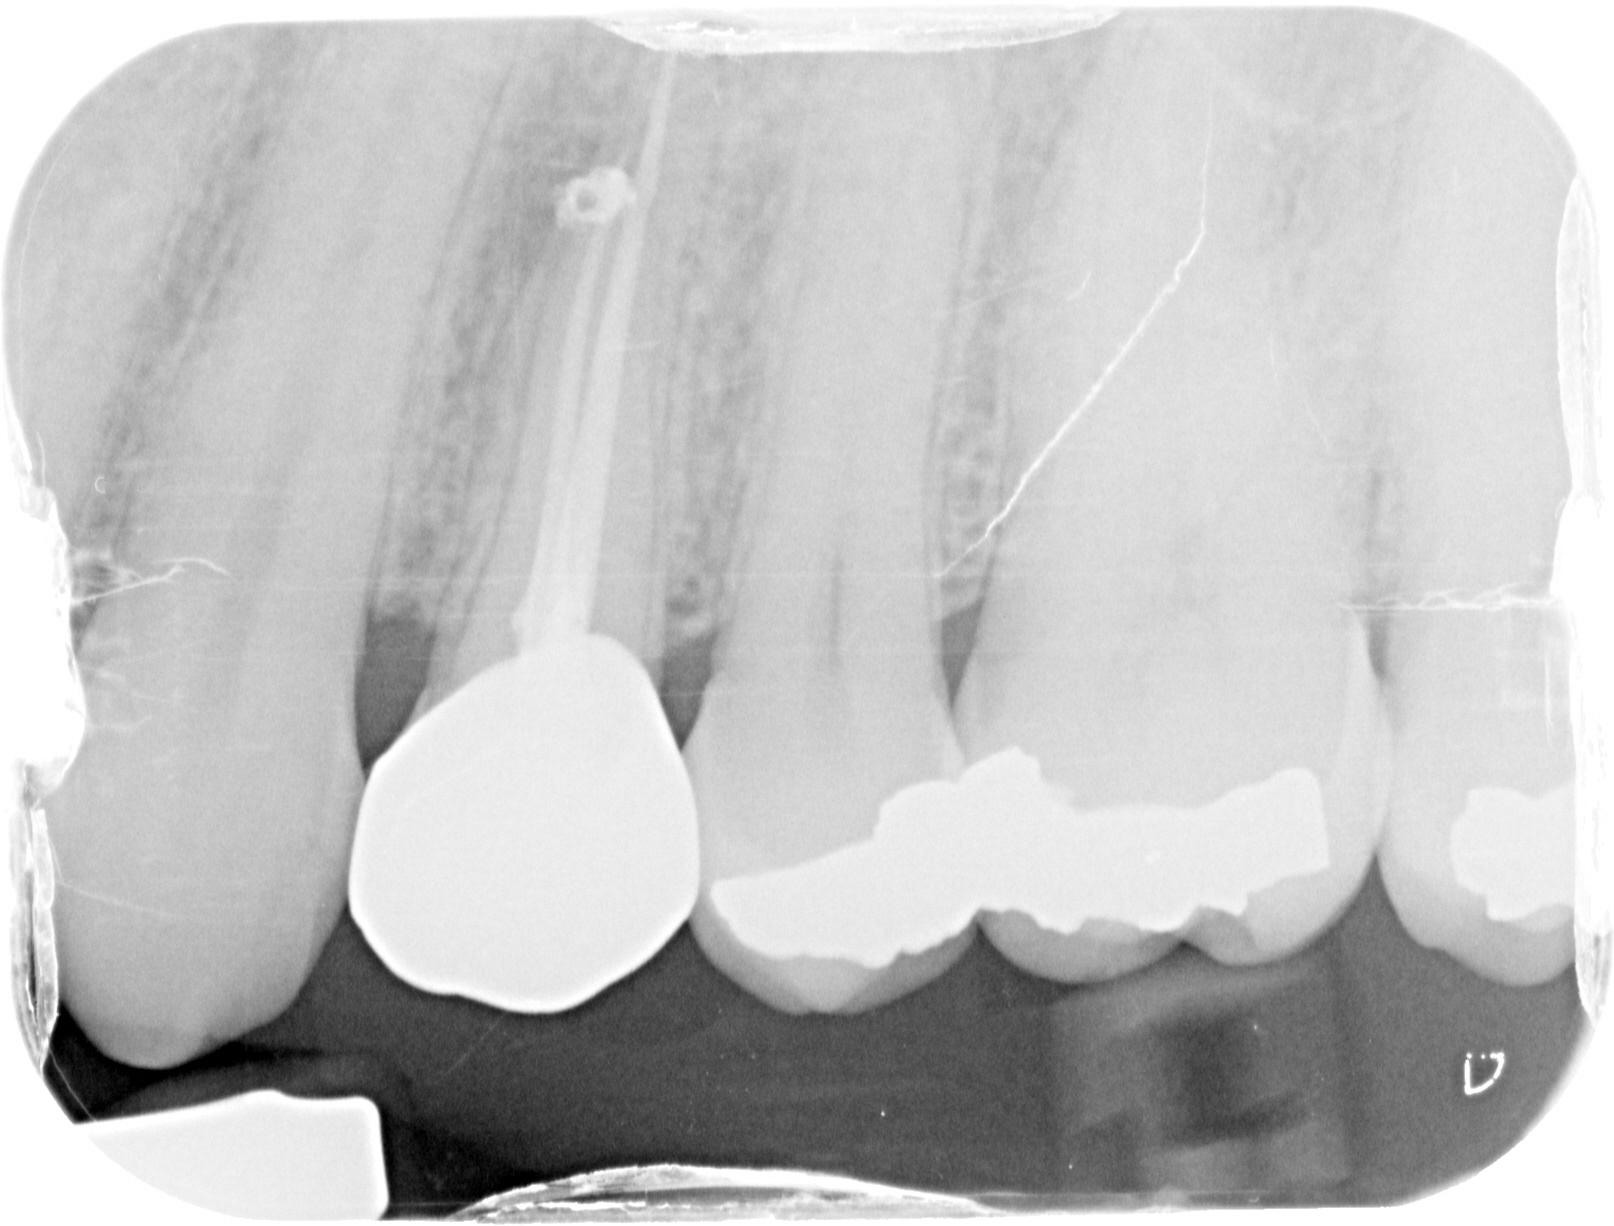

SUCCESSFUL 14

INITIAL